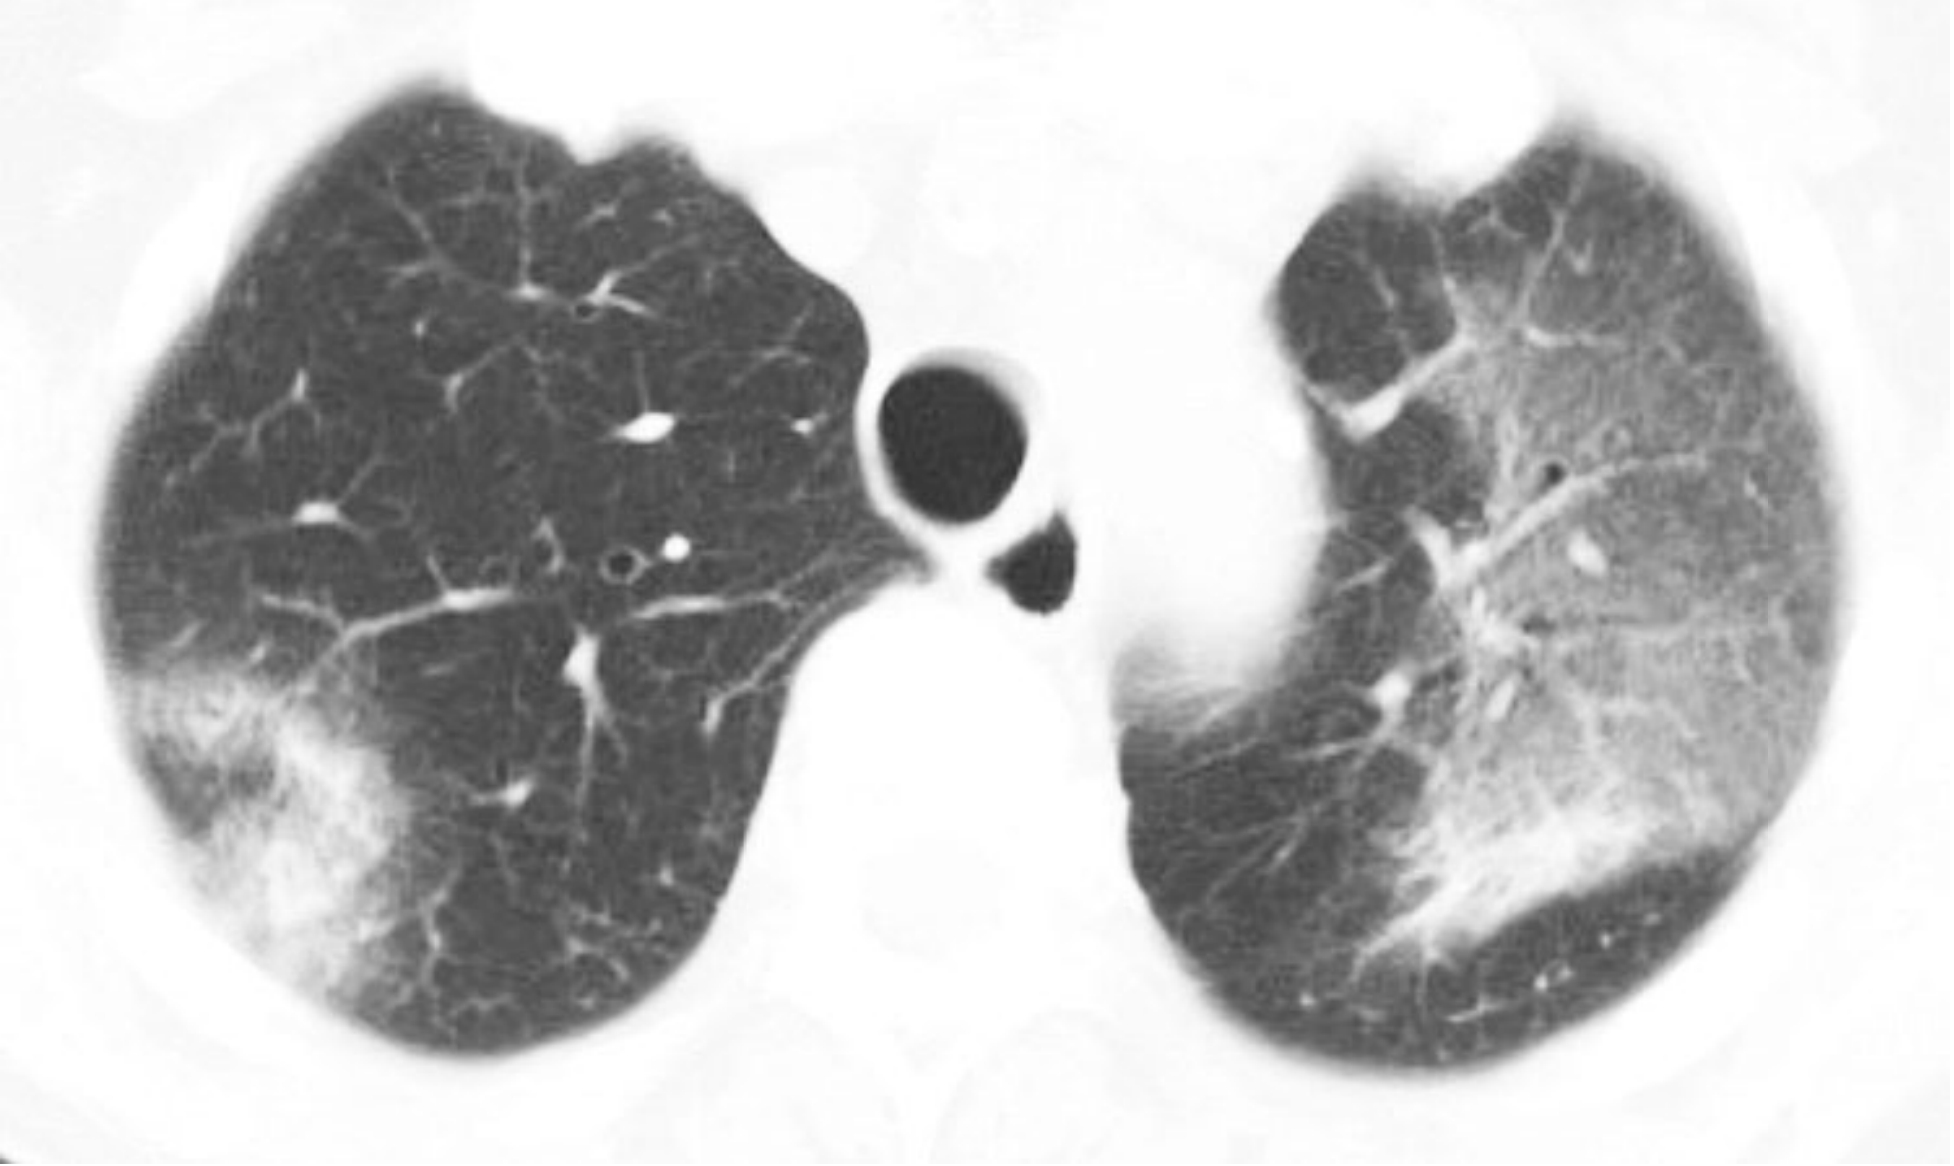

间质性肺炎的HRCT表现取决于炎症或者纤维化的程度。以炎症为主的病例表现为磨玻璃影(GGO)和(或)实变。以纤维化为主的病例表现为不规则网状影、牵拉性支气管扩张和(或)蜂窝征。

虽然在某些病例中可能存在明显的炎症和纤维化成分,但是大部分间质性肺炎通常以两者之一为主要表现。普通型间质性肺炎(UIP)以肺纤维化为主要特征,非特异性间质性肺炎则可能表现为纤维化型或细胞型或两者兼有。其余的间质性肺炎则以炎症为主,但是部分病例可能向纤维化进展。

eb8e21eebff9ef7cc5bf91aa43df6ecf.png

炎症与纤维化的HRCT不同表现。

间质性肺炎表现为不同程度的炎症和纤维化;A和B. 2例结缔组织病患者的非特异性间质性肺炎。

A.HRCT显示GGO,无明显的纤维化征象,提示潜在可逆的炎症性病变;

B.HRCT显示牵拉性支气管扩张(箭)及不规则网状影的纤维化征象,提示对治疗不敏感的肺部瘢痕。